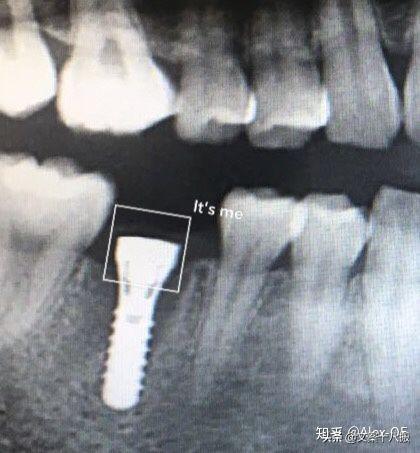

2018年7月6日,下午先拍了CT,很小劑量的輻射。主任方醫(yī)師說我的情況符合植牙條件,骨量也沒有問題,接下來安排了方案并開始手術(shù),由方醫(yī)師操刀,整個(gè)手術(shù)由3個(gè)醫(yī)生共同完成。用消毒水漱口兩分鐘后,躺在那個(gè)椅子上,燈光刺眼,消毒棉花在口腔周圍一圈一圈得涂,鼻子上都涂了。身上蓋了做手術(shù)的綠布(這個(gè)布有名稱嗎?),只露出口腔。因?yàn)檠劬σ苍诰G布底下,所以手術(shù)全程看不到醫(yī)生用過哪些工具,只能想象醫(yī)生在干什么,做了麻醉感覺不到切開牙齦,鉆孔的疼痛,但是植入牙體是有感覺的,畢竟那么大的東西硬生生的塞了進(jìn)去,從醫(yī)生手肘的顫動(dòng)知道這牙題塞進(jìn)牙槽骨挺費(fèi)勁的。術(shù)前忘記看時(shí)間了,估計(jì)今天整個(gè)過程開始到結(jié)束大概40分鐘,40分鐘內(nèi)還包括了十幾分鐘的醫(yī)生的清潔準(zhǔn)備工作。沒有什么不適,不過醫(yī)生有一會(huì)兒手碰巧壓住鼻子上面的綠布了,就只能用嘴呼吸了。我也沒提醒醫(yī)生覺得很快就過去了,醫(yī)生說有任何不適可以隨時(shí)叫停。(因?yàn)樵谇鍧嵉木G布底下,隨意抬手示意會(huì)造成污染,能不停就別停了,真的有不適吱聲就行)沒告訴他,大概憋了快一分鐘氣覺得種牙還沒有拔牙痛,只是長(zhǎng)時(shí)間張著嘴比較難受,術(shù)后拍片醫(yī)生說果不錯(cuò),配了消炎藥和漱口水,臉貼著冰袋回去了,一周后拆線?,F(xiàn)在已經(jīng)過去8個(gè)小時(shí)了,麻醉藥也過了,有少量滲血,但疼痛感十分輕微。植牙回去以后,怕麻醉藥過去后疼,下午2點(diǎn)植入后敷冰袋到了晚上8點(diǎn)。那時(shí)候確實(shí)感覺到疼,不過是輕微而持續(xù)的疼,并且這種輕微的疼大概持續(xù)了四天,術(shù)后配的藥也差不多吃完,那之后就沒事了。

2018年8月15日,距離植入牙根一個(gè)多月過去了,現(xiàn)在可以舔到那個(gè)缺牙的中間有個(gè)硬東西。它像個(gè)螺釘,上面有個(gè)釘帽,打開這個(gè)帽子是內(nèi)螺紋,到時(shí)候用來固定牙冠的?,F(xiàn)在是漫長(zhǎng)的等待時(shí)間,等人造牙根和我的牙槽骨長(zhǎng)在一起,醫(yī)生說大概3-5個(gè)月后去做牙冠。現(xiàn)階段要注意牙齒的清潔(哪時(shí)候都要,只是現(xiàn)在怕了,特別重視刷牙),從6月開始用上了菲利普的電動(dòng)牙刷,感覺不錯(cuò)的,比手動(dòng)干凈,剛開始震的不習(xí)慣,用久了發(fā)現(xiàn)很舒服。

2018年11月3日,距離植體植入大概4個(gè)月,愈合時(shí)間夠了,開始牙冠部分。當(dāng)天就漱漱口,把一盒子橡皮泥(好像叫“牙齒硅橡膠取印?!保浚┮粯拥臇|西扣在牙上取模,上下兩排牙都一樣做法。另外又單取了一小團(tuán)橡皮泥專門用來取我缺的那個(gè)牙位的模型。這天的時(shí)間很快,不麻醉。